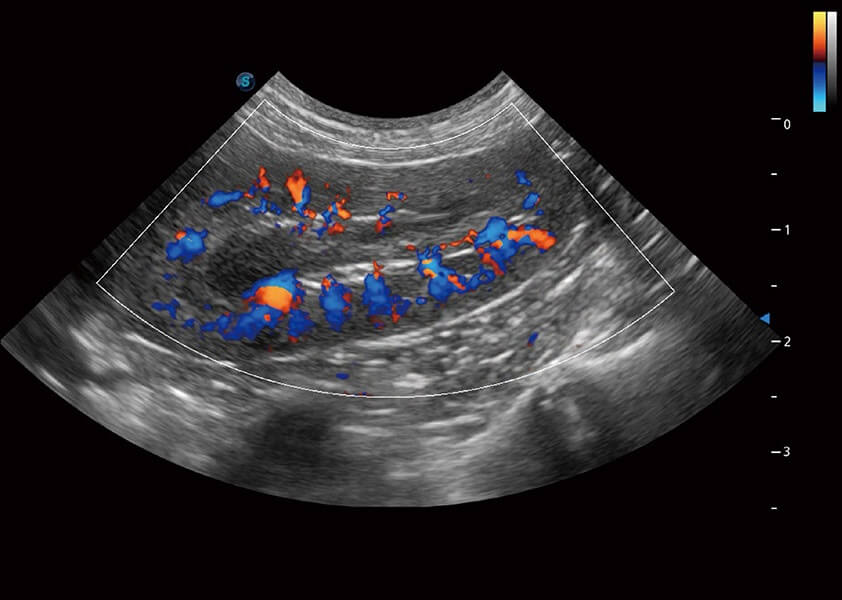

4T血流成像 微察秋毫

融合不同血流成像技术的优势,即可以提升血流成束性,同时可提高血流的视觉敏感性。

SR Flow 高分辨率血流成像

能够清晰显示细小、低速血流图像,获取传统彩色多普勒技术难以得到的细节和信息。

Micro F 显微血流成像

通过创新的Matrix E自适应滤波器和超长时间域算法,极大提升超低速微细血流的检出能力,同时更精准地滤除软组织和噪声信号,为兽用医生提供以往无法通过常规血流获得的疾病诊断信息。

(犬)肾脏血流